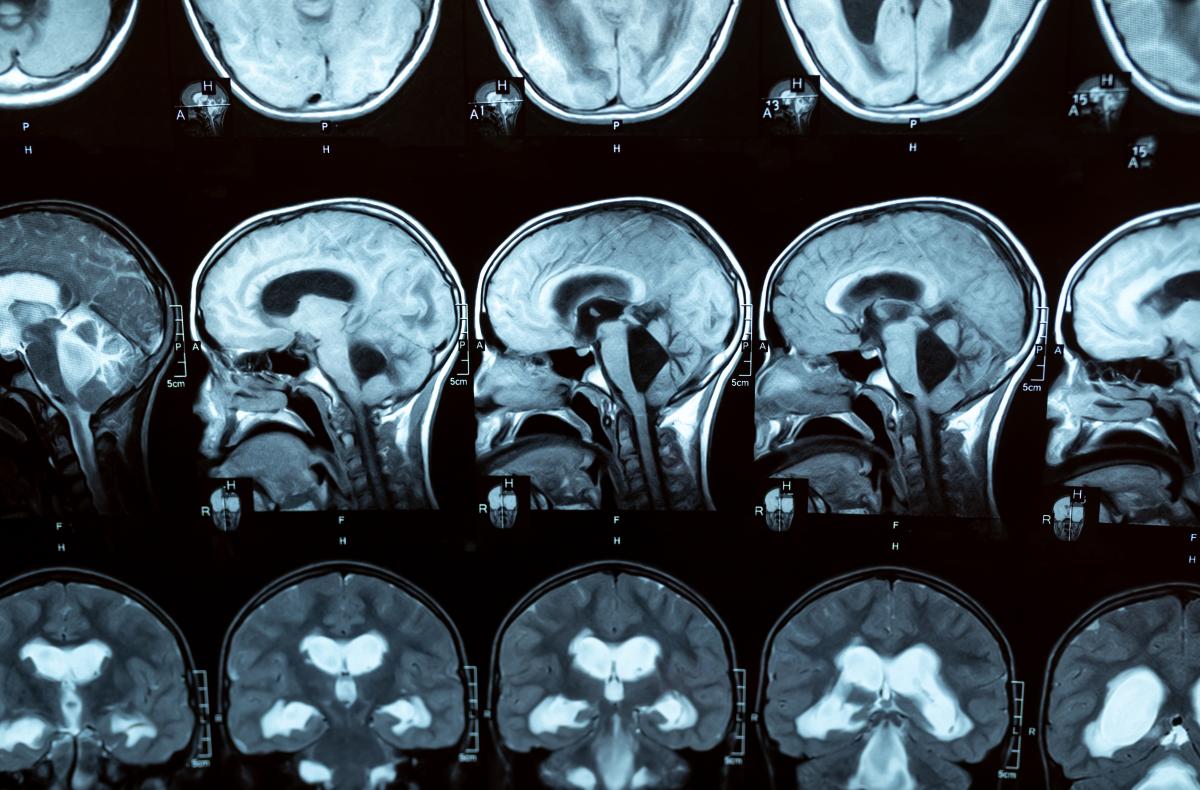

Hydrocephalus scans

Hydrocephalus refers to a build-up of excess fluid in cavities in the brain (called ventricles), causing them to enlarge and possibly increase pressure on the brain. It’s far from uncommon around the world. In the US, around 1 in 500 babies are born with hydrocephalus, with more developing the condition in the first two years of life (the figures for Europe are not directly comparable but are available here). Nor is it restricted to children: in adults the condition can occur at any time, particularly after an intracranial infection or bleeding, or after the age of 60, with increasing prevalence with age. In fact, it is quite likely to be underdiagnosed in this age group, when symptoms may be ascribed to Alzheimer’s or Parkinson’s disease. Which of course means that many people – up to 10% of dementia patients  – could be living with a treatable condition, not a degenerative one. Just think of what that could mean for quality of life, not only for the sufferers, but for their loved ones and carers.